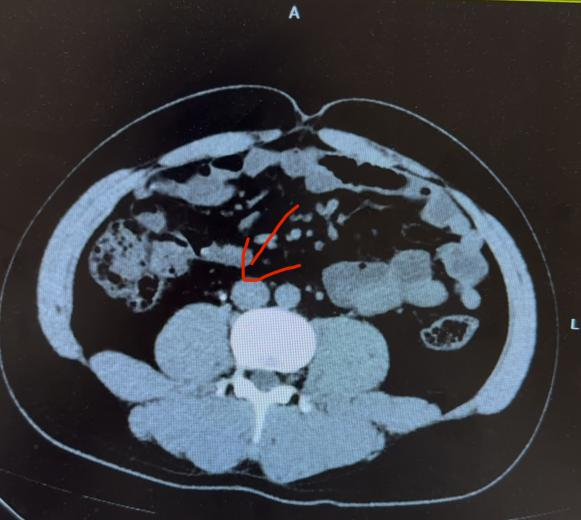

情况紧急,医护人员迅速为他进行超声检查,很快就找到了罪魁祸首——一枚卡在输尿管的结石。

(图片引用自网络)